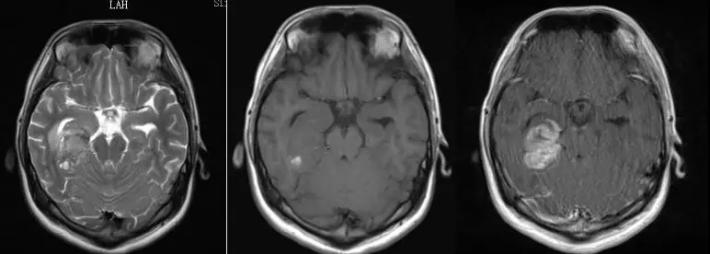

病史简介 患者男,18岁,因“久站后双小腿不自主颤动10余天”于2018.6.22入院。 患者十余天前无明显诱因下出现久站后双小腿不自主颤动,呈无力状。休息后可缓解。自觉体育运动能力较前有下降(患者为体校生)。无四肢抽动、无意识丧失、无二便困难。无明确外伤史。 查体: 神清,精神软,四肢肌力V级,深浅感觉无殊。 术前检查: 入院后头颅MRI增强显示:右侧海马占位伴出血,胶质瘤考虑(图1)。MRS:右侧海马病变部位NAA峰明显降低,Cho明显升高,Cho与NAA的比值明显加大。右侧海马病变以肿瘤可能性大。ASL灌注提示右侧海马占位明显高灌注(图2)。

图1.患者术前头颅MRI增强:右侧海马占位伴出血,胶质瘤考虑。